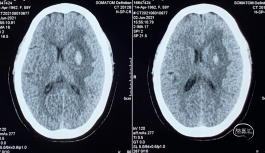

栓塞后即刻影像

工作角度造影显示动脉瘤栓塞致密,LACA A1、ACoA、双A2显影良好,左A2似有血栓(左图)。直头SL-10退至LACA A1末端,推注替罗非班1ml(右图)。

用药后再造影

再造影,发现RACA A2显影差,局部推注替洛非班无效,考虑前交通动脉血流受限,决定支架内球囊扩张。

术后影像

扩张术后造影:显示RACA血流恢复。

术后30分钟造影:LICA正侧位显示良好。

术后支架重建及蒙片:显示支架完全打开,贴壁充分,动脉瘤栓塞致密。